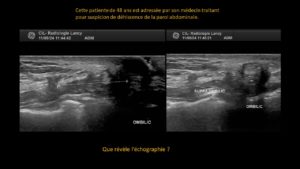

Aspect tuméfié et infiltré de la glande lacrymale gauche au sein de laquelle on individualise une structure kystique antéro-inférieure mesurée à 7 x 4 mm de diamètre dans le plan transversal et 6 mm de longueur. Absence de restriction de la diffusion* et baisse de l’ADC*. Rehaussement* périphérique englobant les prolongements antérieur et postérieur.

À l’échographie ci-dessus, les “septats” intra-kystiques se traduisent par des structures linéaires millimétriques hyperéchogènes* pouvant en imposer pour une origine ciliaire.

Conclusion

Lésion kystique infra-centimétrique développée au sein de la glande lacrymale gauche totalement infiltrée, de même les parties molles sous-cutanées, ce qui fait évoquer une origine rétentionnelle à type de Dacryops. L’hypothèse d’une incrustation pilleuse avec transformation kystique secondaire est probable.